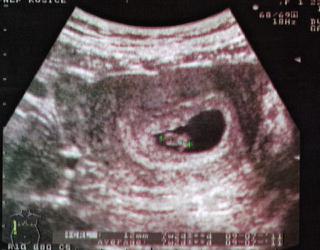

no a zabudla som, tu je nasa foto

ja som este nic nepocula a videla len taku gulicku v bublinke 🙂 ale aj tak bola krasna 😀

@lenka.s krasna foto 🙂

ja som tam mala len taku minigulicku zatial 😀